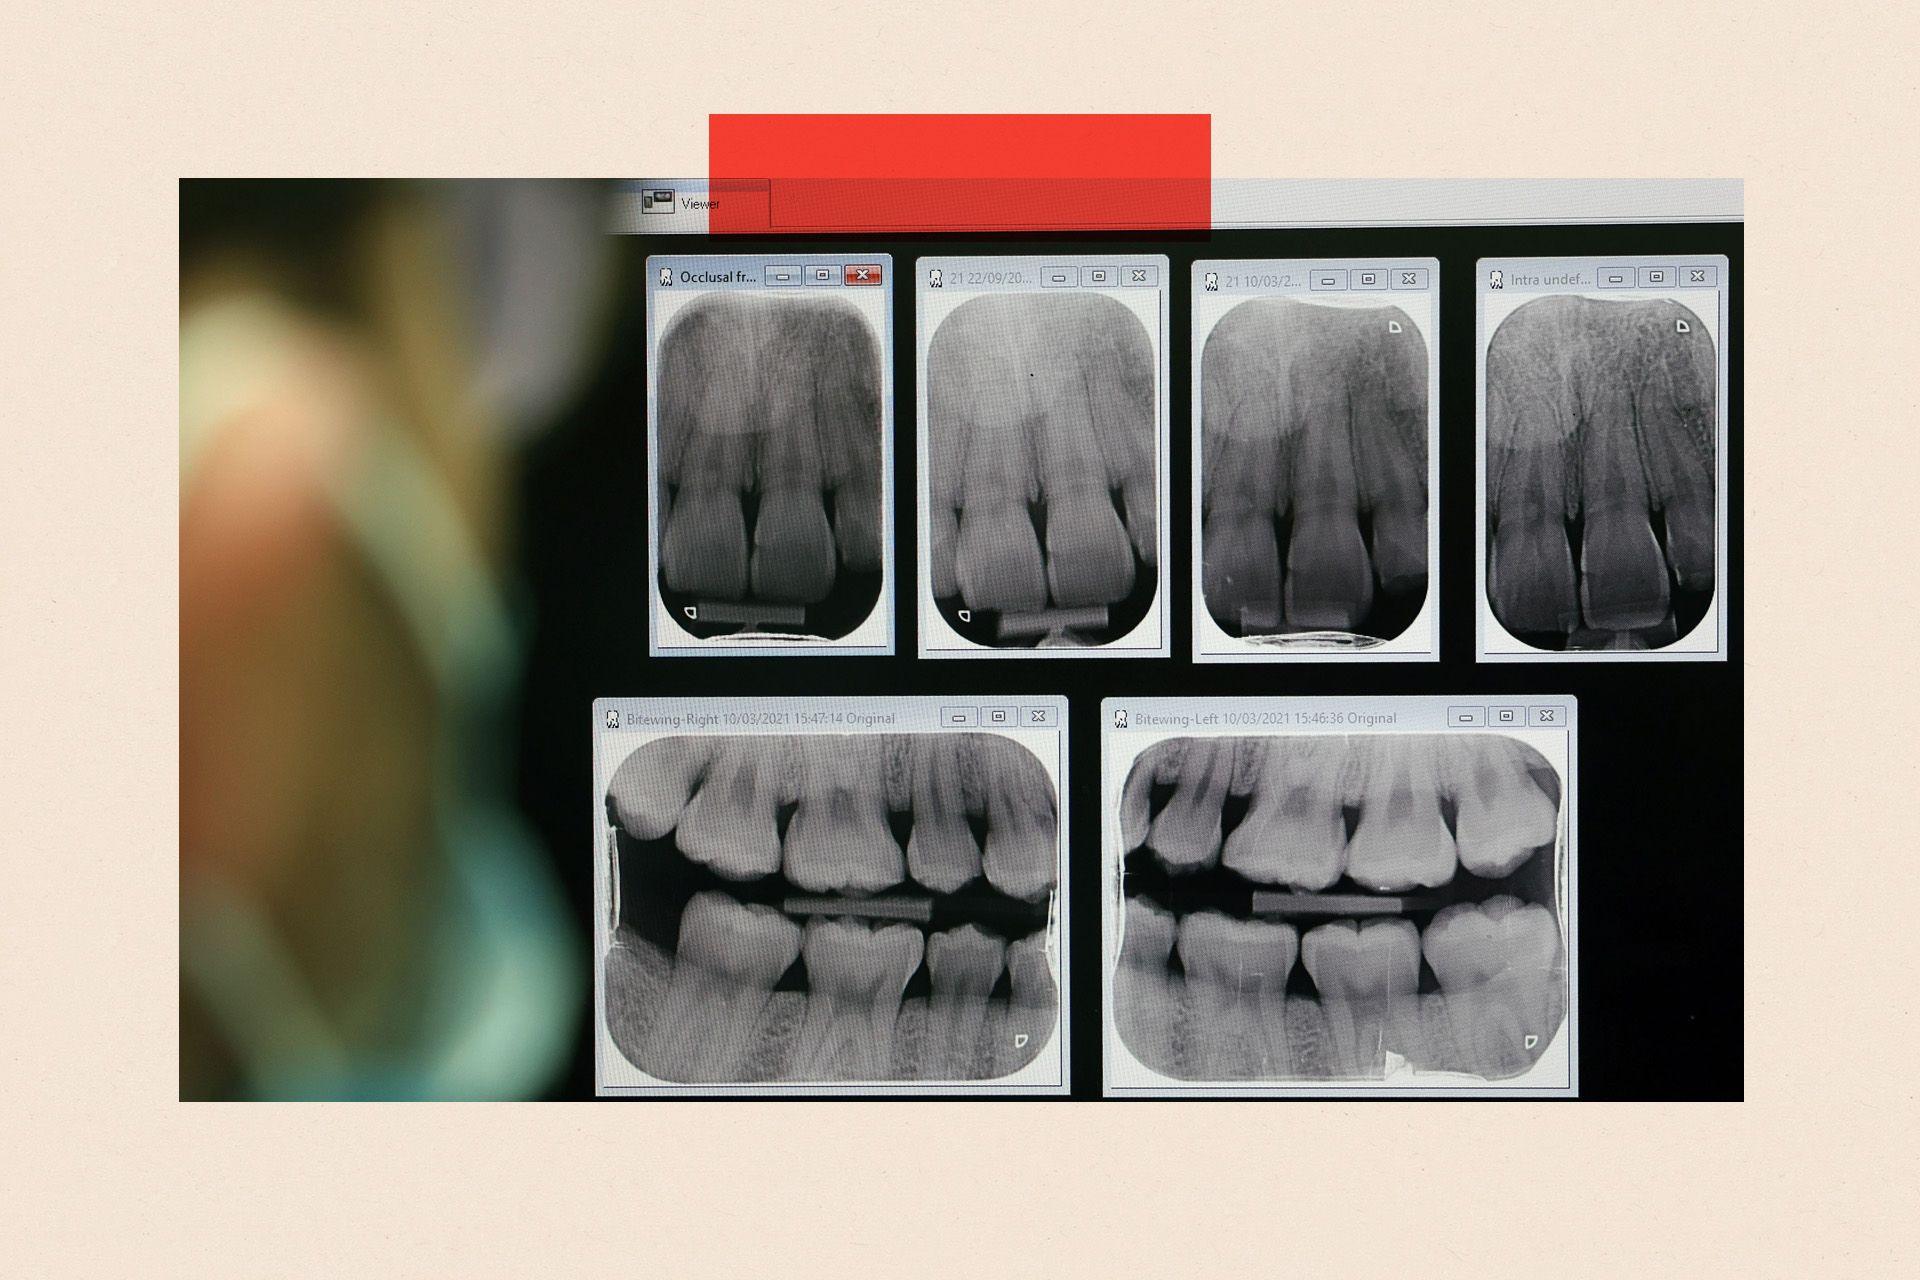

Official data shows that more complex care, in particular, has become much harder to access on the NHS. Over the last ten years, the number of routine NHS examinations has fallen by 6% in England while the number of root canals, where an infection is removed from deep inside the tooth, has dropped by 49%.